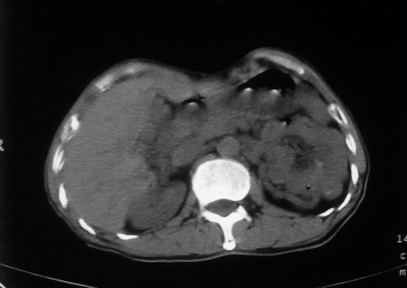

男,66岁,贲门ca术后一年,喝了5、6杯水了。怎么描述跟诊断啊